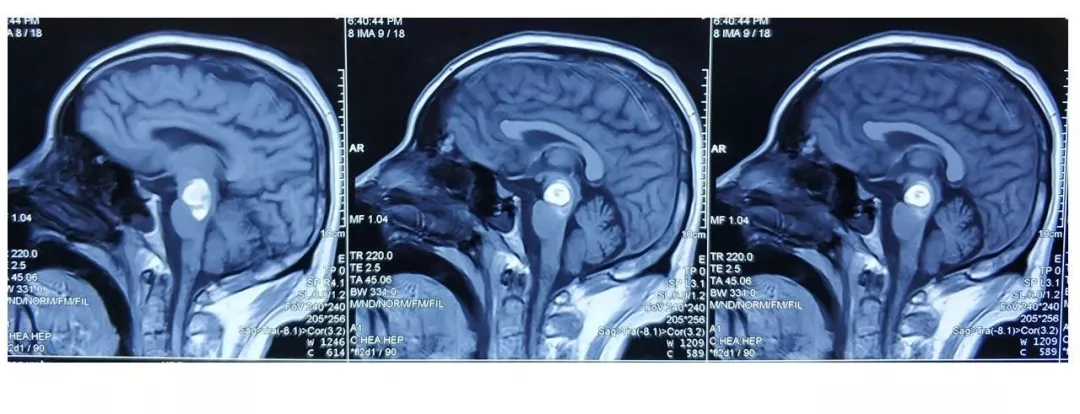

入院后完善CTA,DSA等检查提示颅内多发动脉瘤:

其中右侧颈内动脉眼段动脉瘤(约13.8*14mm大小,瘤颈8.04mm)。和家属沟通病情,告知介入和开颅手术两种治疗方式的风险利弊后,患者家属选择开颅右侧眼动脉段动脉瘤夹闭手术治疗。

进一步行DSA+CT融合,模拟手术入路视角。